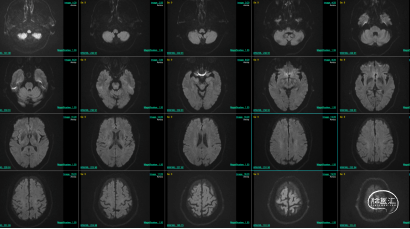

术前DWI。